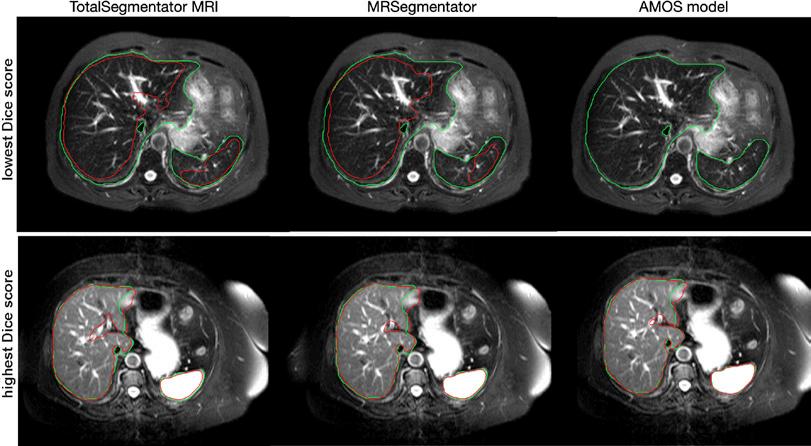

Figura 5. Imágenes de resonancia magnética axial de los casos con la puntuación Dice más baja (arriba) y más alta (abajo) en el conjunto de pruebas externas CHAOS para nuestro modelo propuesto, TotalSegmentator MRI, así como para dos modelos de referencia disponibles públicamente, MRSegmentator y AMOS. La segmentación de referencia para el hígado y el bazo se muestra en verde, y la segmentación del modelo se muestra en rojo. El conjunto de datos CHAOS se utilizó para mostrar los mejores y los peores resultados porque este conjunto de datos es el más independiente de los datos de entrenamiento de los tres modelos.